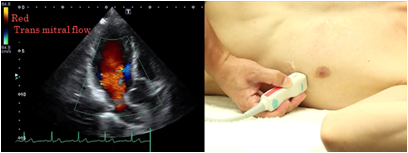

Color Doppler method

With the color Doppler method, blood flow towards the probe is displayed red, the flow away from the probe is displayed blue: the brighter the hue, the faster the relative velocity. For gain adjustment of color Doppler imaging, you should raise the gain until noise appears and then decrease it until the noise disappears to make observations and recordings. Adjust without widening the color display area more than necessary because the frame rate is reduced and real time performance falls when it is adjusted too wide.